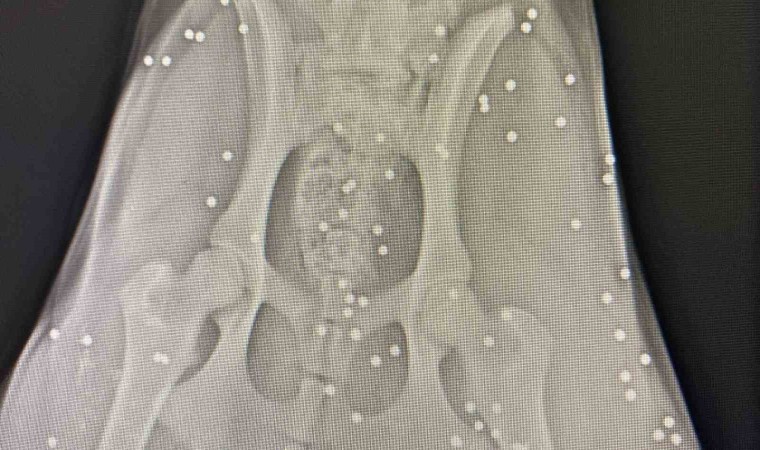

Antalya’nın Aksu ilçesinde silahla vurulan sokak köpeğinin çekilen röntgen görüntüsü adeta şoke etti. Yapılan incelemede köpeğin kalçasında onlarca saçmaya rastlanırken, veterinerde ilk müdahalesi yapılan köpek, bir hayvansever tarafından bakımı üstlenildi.

Olay, Aksu ilçesi Solak Mahallesi Hasan Tahsin Caddesi üzerinde meydana geldi. Alınan bilgiye göre, sokak üzerinde iki el silah sesi duyan Gülhan Tünay, bir süre sonra yanına bir sokak köpeğinin acı içerisinde geldiğini gördü. Tünay’ın ilk incelemesinde sokak köpeğinin üzerinde kan izlerine rastlandı. Köpeğin vurulmuş olabileceği ihtimali üzerinde durarak veterinere götüren Tünay, kalçasından çekilen röntgen görüntüsüyle adeta hayatının şokunu yaşadı. Yapılan incelemede köpek üzerinde onlarca saçmaya rastlandı. İlk müdahalesi ilçede bulunan klinikte Veteriner Hekim Mustafa Gülcü tarafından yapılan sokak köpeği, Tünay tarafından sahiplenilerek eve götürüldü.

Polis ekipleri ise şikayet üzerine harekete geçerek olayla ilgili inceleme başlattı. Köpeğin durumu hakkına açıklama yapan Veteriner Mustafa Gülcü, “Köpek bize silahla yaralanma şikayetiyle geldi. Biz hemen ilk müdahalesini yaptık. Ardından röntgen çektik, incelediğimizde çok sayıda saçmaya rastladık. Yakın mesafeden sıkılsa sinirlerine zarar verebilirdi” sözlerine yer verdi.

“Röntgen görüntülerine baktığımızda köpeğin arka kısmı tamamen yok”

Yaşananları anlatan Gülhan Tünay, “Sabah saatleriydi iki el silah sesi duydum. Ardından köpeği acı içerisinde buldum. Eşime seslenerek eyvah köpeği vurdular dedim. Köpek arka tarafı kanlar içinde geldi. Seçim gecesi de bir köpek vurulmuştu, o köpek şuan ampute oldu. Veterinere söyledim gelip aldılar. Daha sonra polisi aradım ve köpeği vuran kişiden şikâyetçi oldum. Röntgen görüntülerine baktığımızda köpeğin arka kısmı tamamen yok. Kaç tane saçma olduğunu bilmek zor. Şuan durumu çok iyi değil, ilk getirdiğimizde hayati tehlikesi vardı. Şuan serum takılı biz de bekliyoruz. İnşallah özürlü kalmaz. Ne hissettiğini bilmiyorum. İnsanların artık silahlanması önlensin istiyorum” dedi.